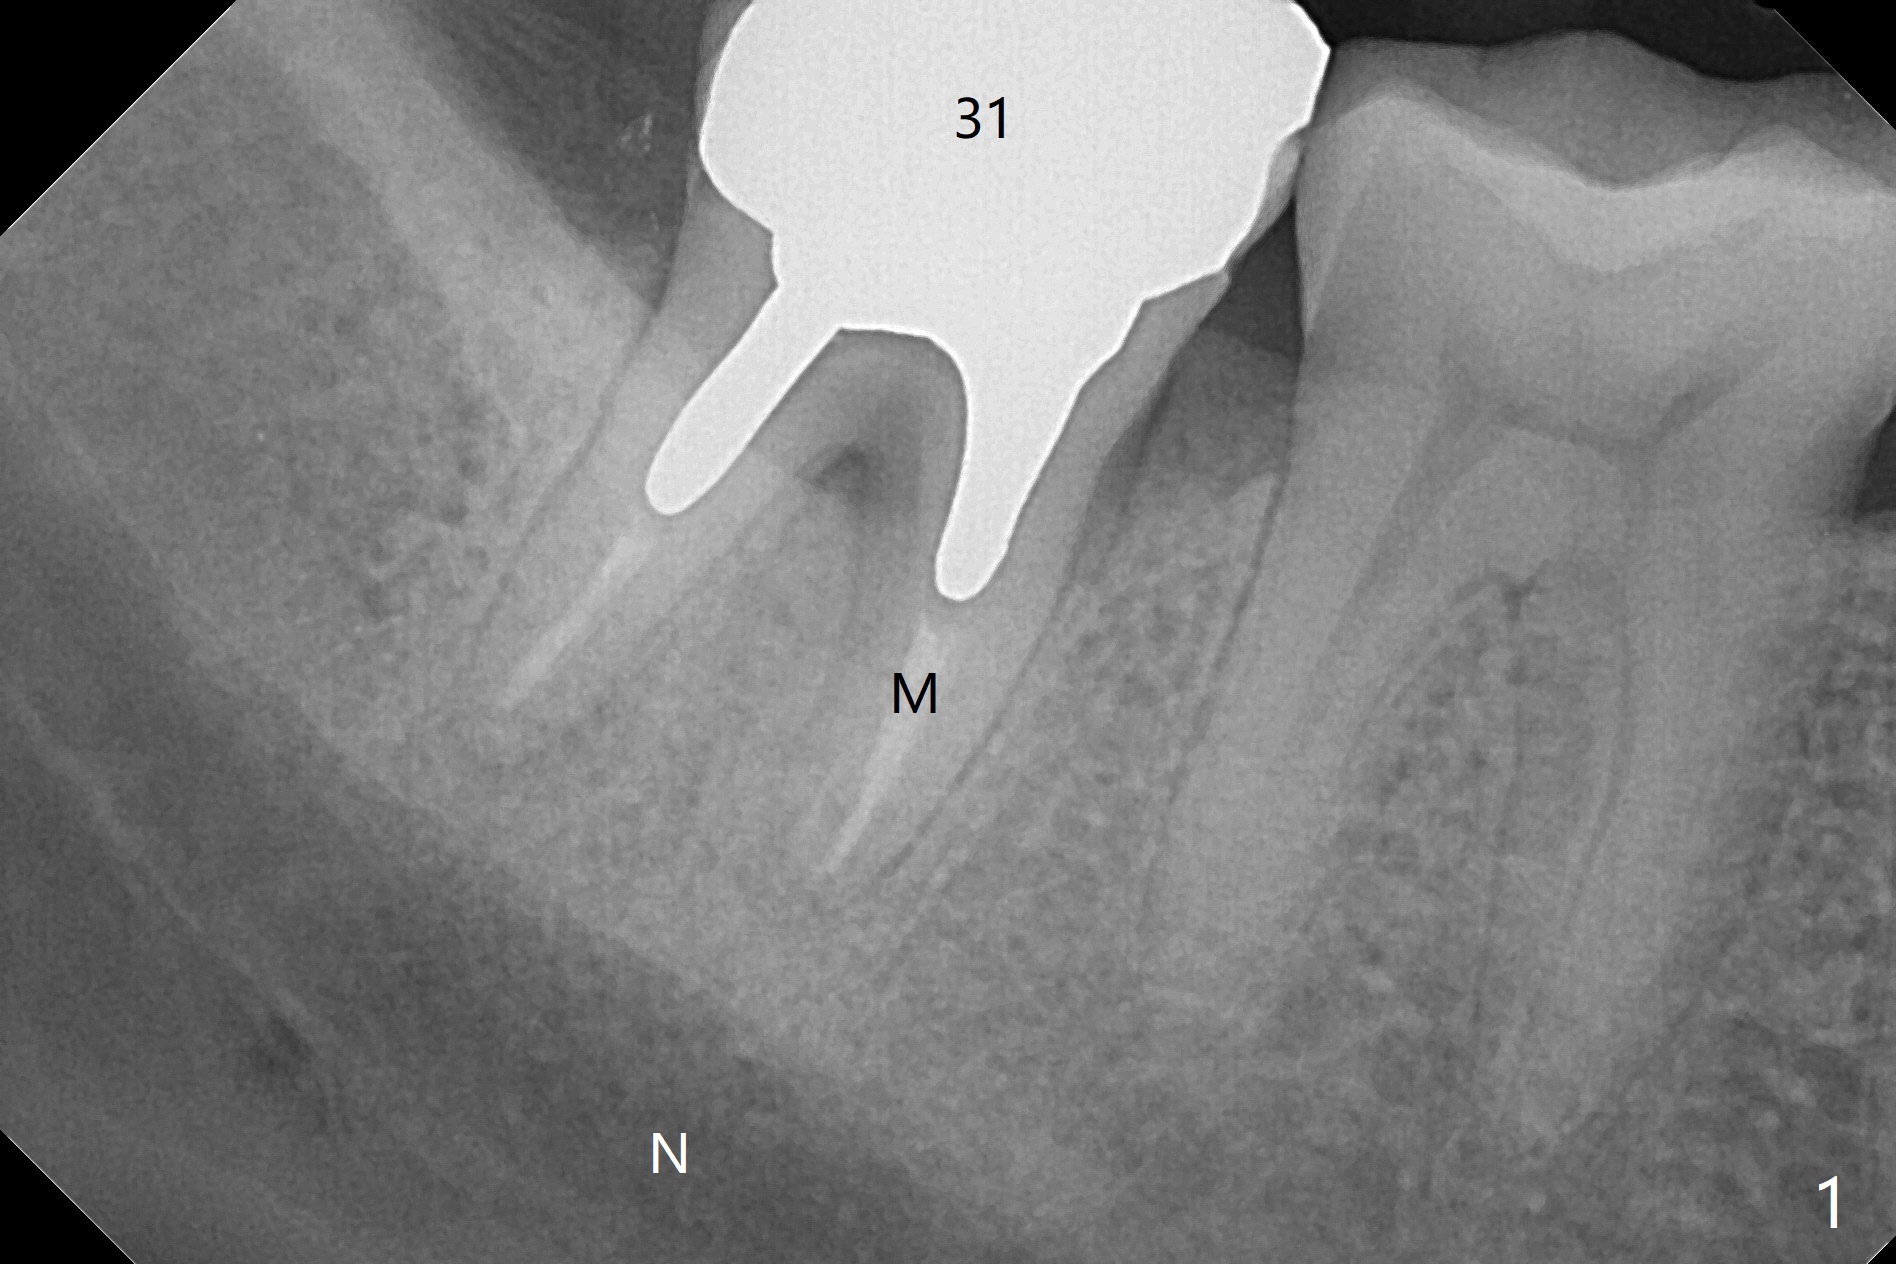

36岁女,右下第二磨牙颊侧瘘道,近中牙槽窝(图一:M)离下牙槽神经远,将是种植位点。图二是该牙CT3维横断面,显示近中(M),远中(D)牙根之间颊侧(L: 舌侧)连接(*);牙齿拔除后,牙槽窝成C型(图三,面对舌侧);由于颊侧骨板(图四:B)中断,缺损,植体将植入近中舌侧牙槽窝(绿色,导板)。优点便是三面骨质包绕(rao,图五),只有颊侧需要大量粘性骨粉(图六:*)。